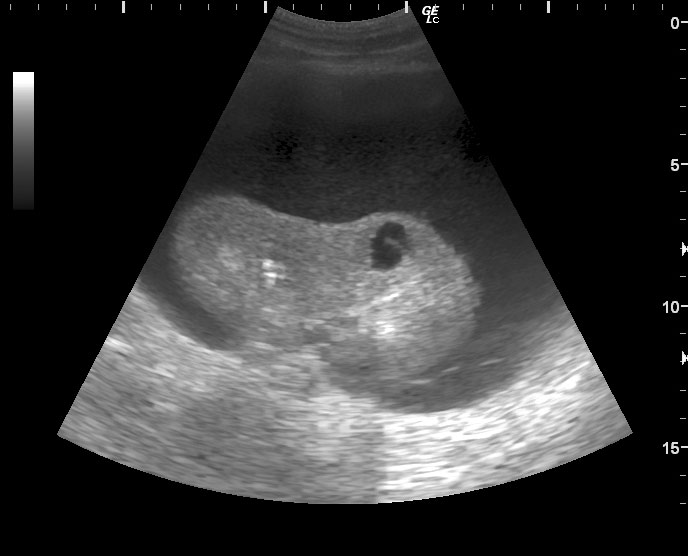

Мужчина средних лет, боли в животе, больше слева. При УЗИ панкреас изменения, характерные для острого панкреатита.

Левая почка:

Что это может быть?

Панкреонекроз хвоста поджеледочной железы с расплавлением паранефральной клетчатки слева, гнойный паранефрит, возможно, с аррозивным кровотечением.

В тот же день это скопление жидкости было задренировано. Получили прозрачную жидкость желтоватого цвета с высоченным уровнем альфа-амилазы (25000).